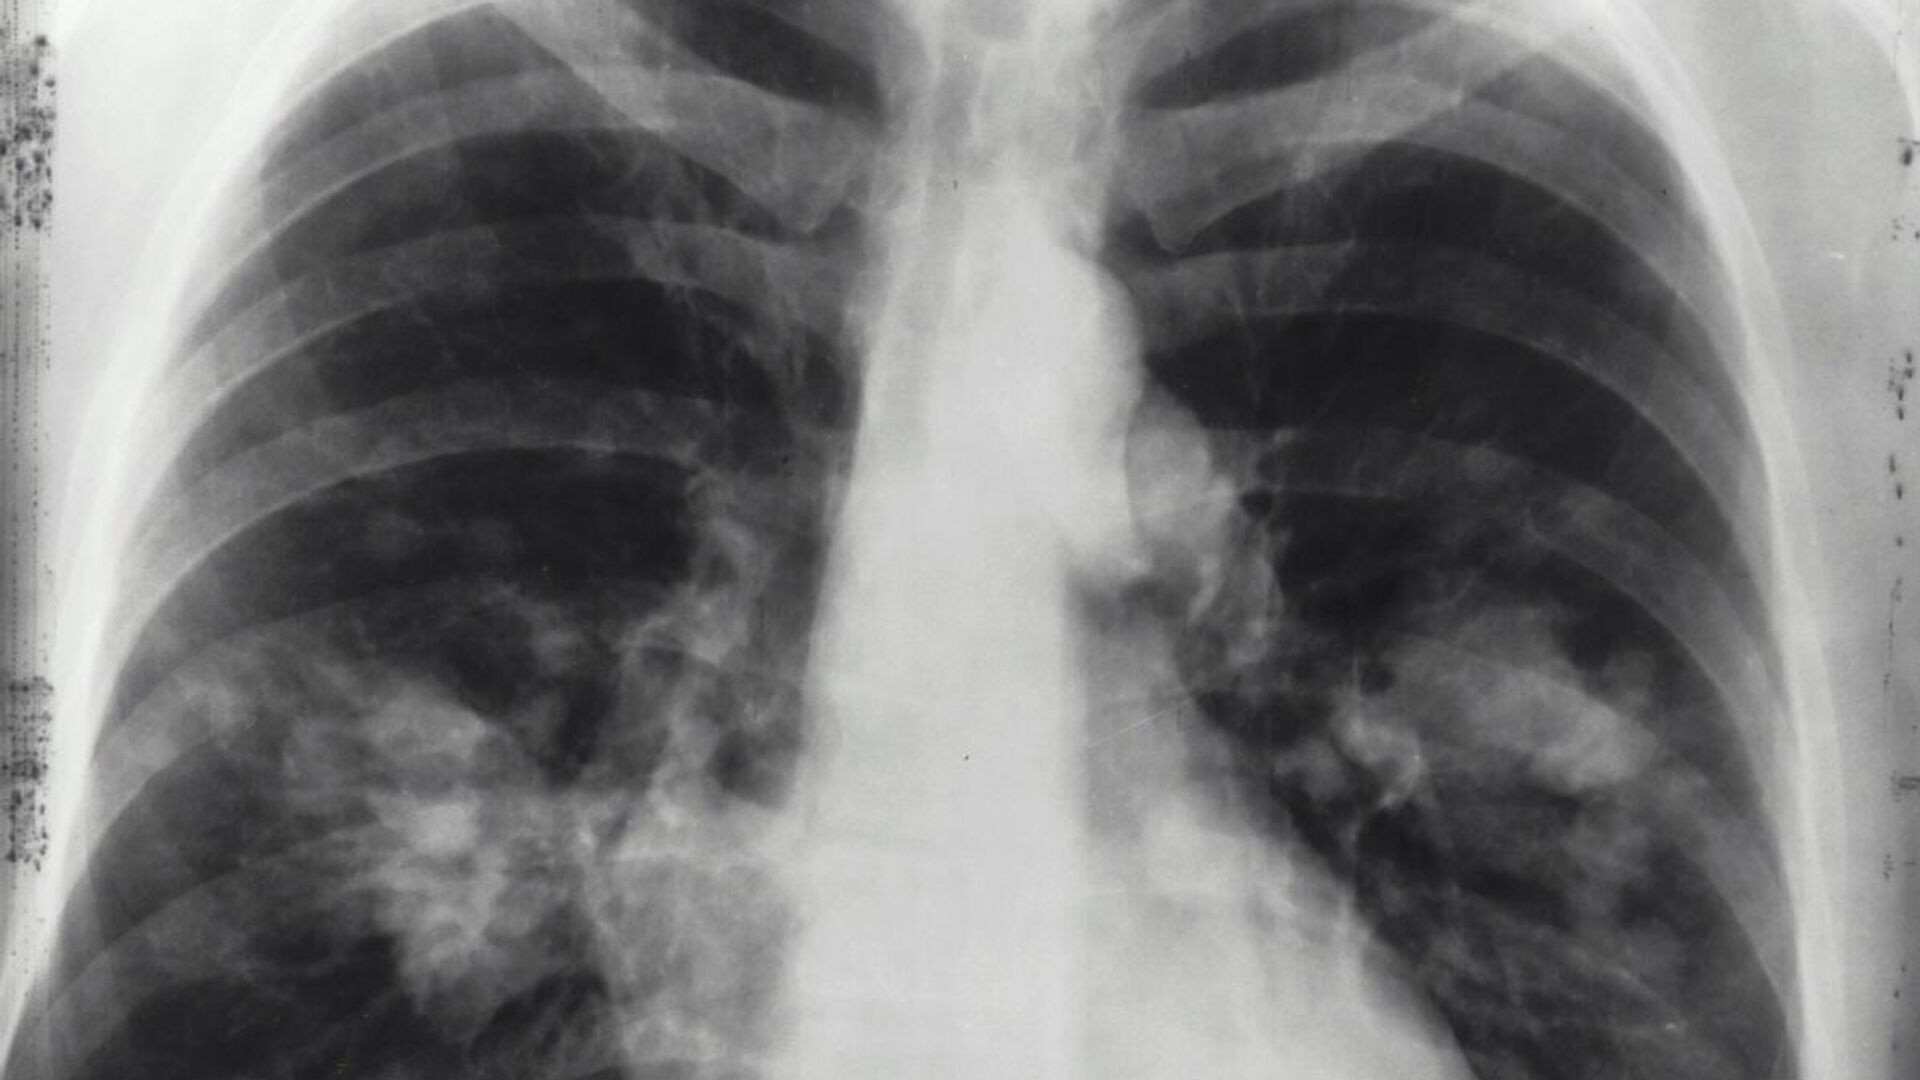

21:23 GMT 15.02.2025 (تم التحديث: 05:02 GMT 16.02.2025) كشفت دراسة جديدة عن تزايد مقلق في حالات الإصابة بسرطان الرئة بين غير المدخنين، خاصة في مناطق شرق آسيا وبالأخص في الصين، وهو من أكثر الأمراض فتكا، ويتسبب في ما يقارب مليوني وفاة سنويا.

ويُرجع الباحثون هذه الظاهرة، إلى تزايد مستويات التلوث البيئي، وتأثيره السلبي على الصحة العامة.

واستندت الدراسة إلى بيانات من المرصد العالمي للسرطان (GLOBOCAN) 2022، بالإضافة إلى سجلات سابقة تغطي الفترة بين عامي 1988 و2017، والتي أظهرت أن سرطان الغدة الدرقية هو النوع الأكثر انتشارا من سرطان الرئة عالميا، إذ يمثل 45.6% من الحالات لدى الرجال، و59.7% لدى النساء، ويعد هذا النوع من السرطان أكثر شيوعا بين غير المدخنين، على الرغم من إمكانية ارتباطه بالتدخين أيضا، وفقا

لموقع "Science Alert".

كما كشفت الدراسة عن اتجاه متزايد في حالات سرطان الرئة بين الأشخاص الذين لم يدخنوا أبدا، مما يستوجب التعامل مع هذه الظاهرة بجدية، إلى جانب الجهود المستمرة لمكافحة التدخين وتقليل معدلاته عالميا.

وأكد الباحثون أن سرطان الرئة لدى غير المدخنين، أصبح في الوقت الحالي هو السبب الخامس الأكثر شيوعا للوفيات المرتبطة بالسرطان على مستوى العالم، وهو يظهر بشكل شبه حصري على هيئة سرطان غدي، ويُلاحظ بشكل أكبر لدى النساء والسكان الآسيويين.

وخلصت الدراسة إلى أن أحد الأسباب الرئيسية لهذا الاتجاه التصاعدي، هو ارتفاع مستويات تلوث الهواء، إذ أثبتت العديد من الدراسات السابقة وجود علاقة وثيقة بين سرطان الغدة وتلوث الهواء.

وبرزت مناطق شرق آسيا، خاصة الصين، كأكثر المناطق تأثرا بسبب رداءة جودة الهواء فيها، مما يزيد من خطر الإصابة بهذا النوع من السرطان.

وبينما تتراجع نسبة المدخنين عالميا، فيبدو أن التلوث البيئي بات يشكل تهديدا صحيا متزايدا، إذ يتبين أنه عامل لا يرتبط باختيارات نمط الحياة الشخصية، بل يرتبط بالممارسات البيئية العالمية التي تؤثر على جودة الهواء الذي نتنفسه جميعا.

وشدد معدو الدراسة على أهمية جمع البيانات وتحليلها باستمرار لفهم كيفية تطور سرطان الرئة بمرور الوقت، مما قد يساعد العلماء في تطوير استراتيجيات أكثر فاعلية لمواجهة هذا المرض القاتل، وأوصت الدراسة بضرورة تنفيذ سياسات صارمة للحد من تلوث الهواء، إلى جانب تعزيز حملات مكافحة التدخين، بهدف الحد من انتشار المرض، وحماية الأجيال القادمة من خطره المتزايد.